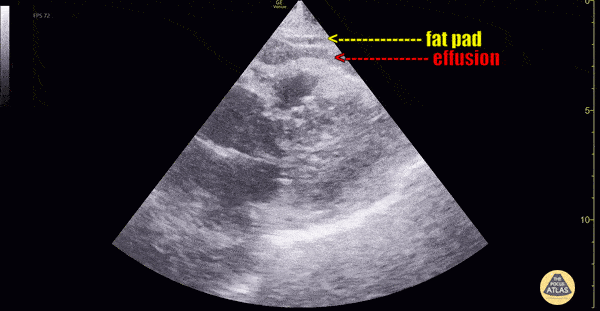

Pericardial fat pad is often mistaken for a pericardial effusion, this clip demonstrates both in the same clip. Pericardial fat pad moves in concert with the heart, while an effusion is circumferential, stationary and does not move in concert with the heart. Multiple cardiac views are helpful in making the diagnosis. Dr. Dimitri Livshits Ultrasound Fellow;Dr. Jane Belyavskaya Ultrasound Fellow;Dr. Chris Hanuscin Ultrasound Fellowship Director